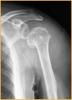

吴XX,女,18岁,右髋疼痛1年,加重1月。 查体:右腹股沟区压痛,前内侧撞击试验(+),4字试验(+) X线片显示:双侧髋臼发育不良。 MRI造影显示:右侧髋臼盂唇损伤,伴盂唇囊肿。